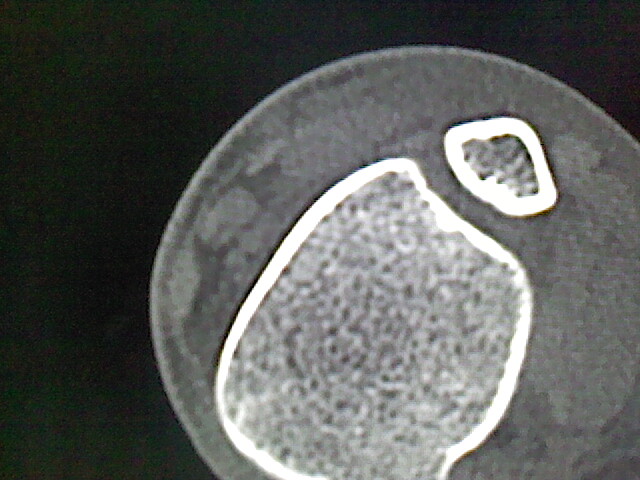

标题: CT17148:男,33岁,左侧胫骨可见一高密度影,大家给看看 [打印本页]

男,33岁,外伤后拍片发现,左侧胫骨可见一高密度影

考虑,右胫骨下端内生性骨瘤。

内生软骨瘤可能

纤维性骨皮质缺损愈合后表现

骨样骨瘤。

可见瘤巢,考虑骨样骨瘤

内生骨瘤可能性大,不知病人有何症状,不除外骨样骨瘤

良性骨肿瘤,以内生软骨瘤或骨纤维瘤可能大。请上传骨窗。